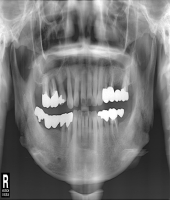

● 진료과목 : [임플란트] 치아상실 후 임플란트

● 내용 : 다수 치아의 상실 후 임플란트 치료